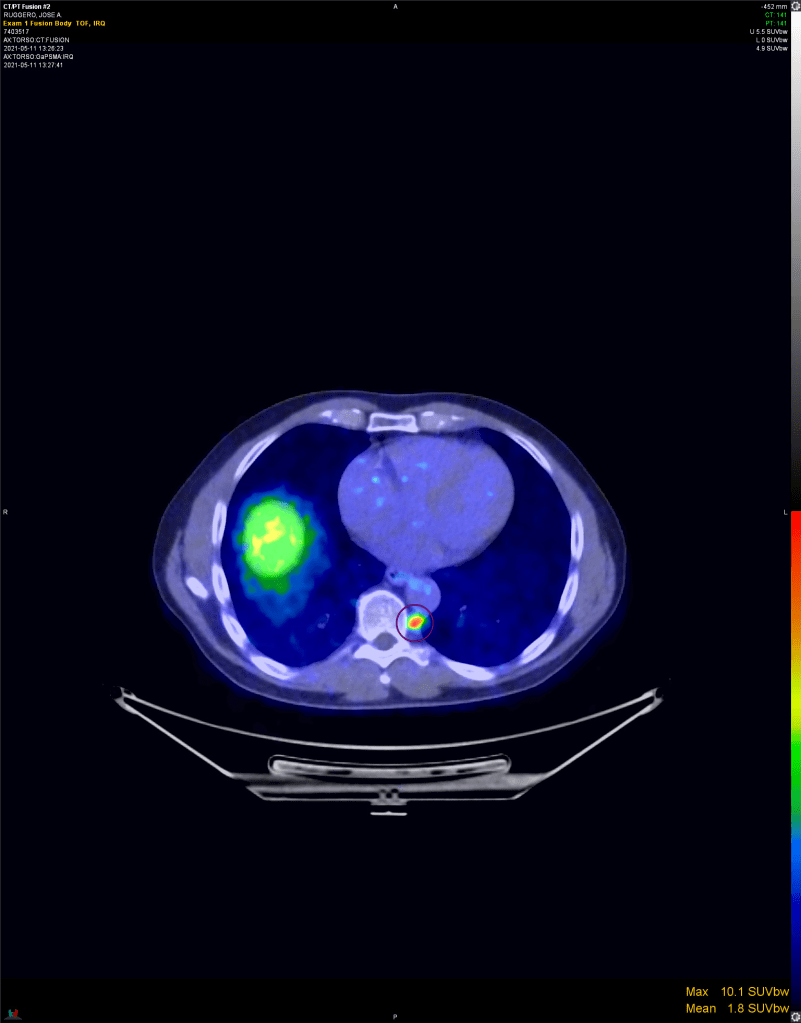

Scan shows the evil glowing red. A horizontal “slice” of my midsection